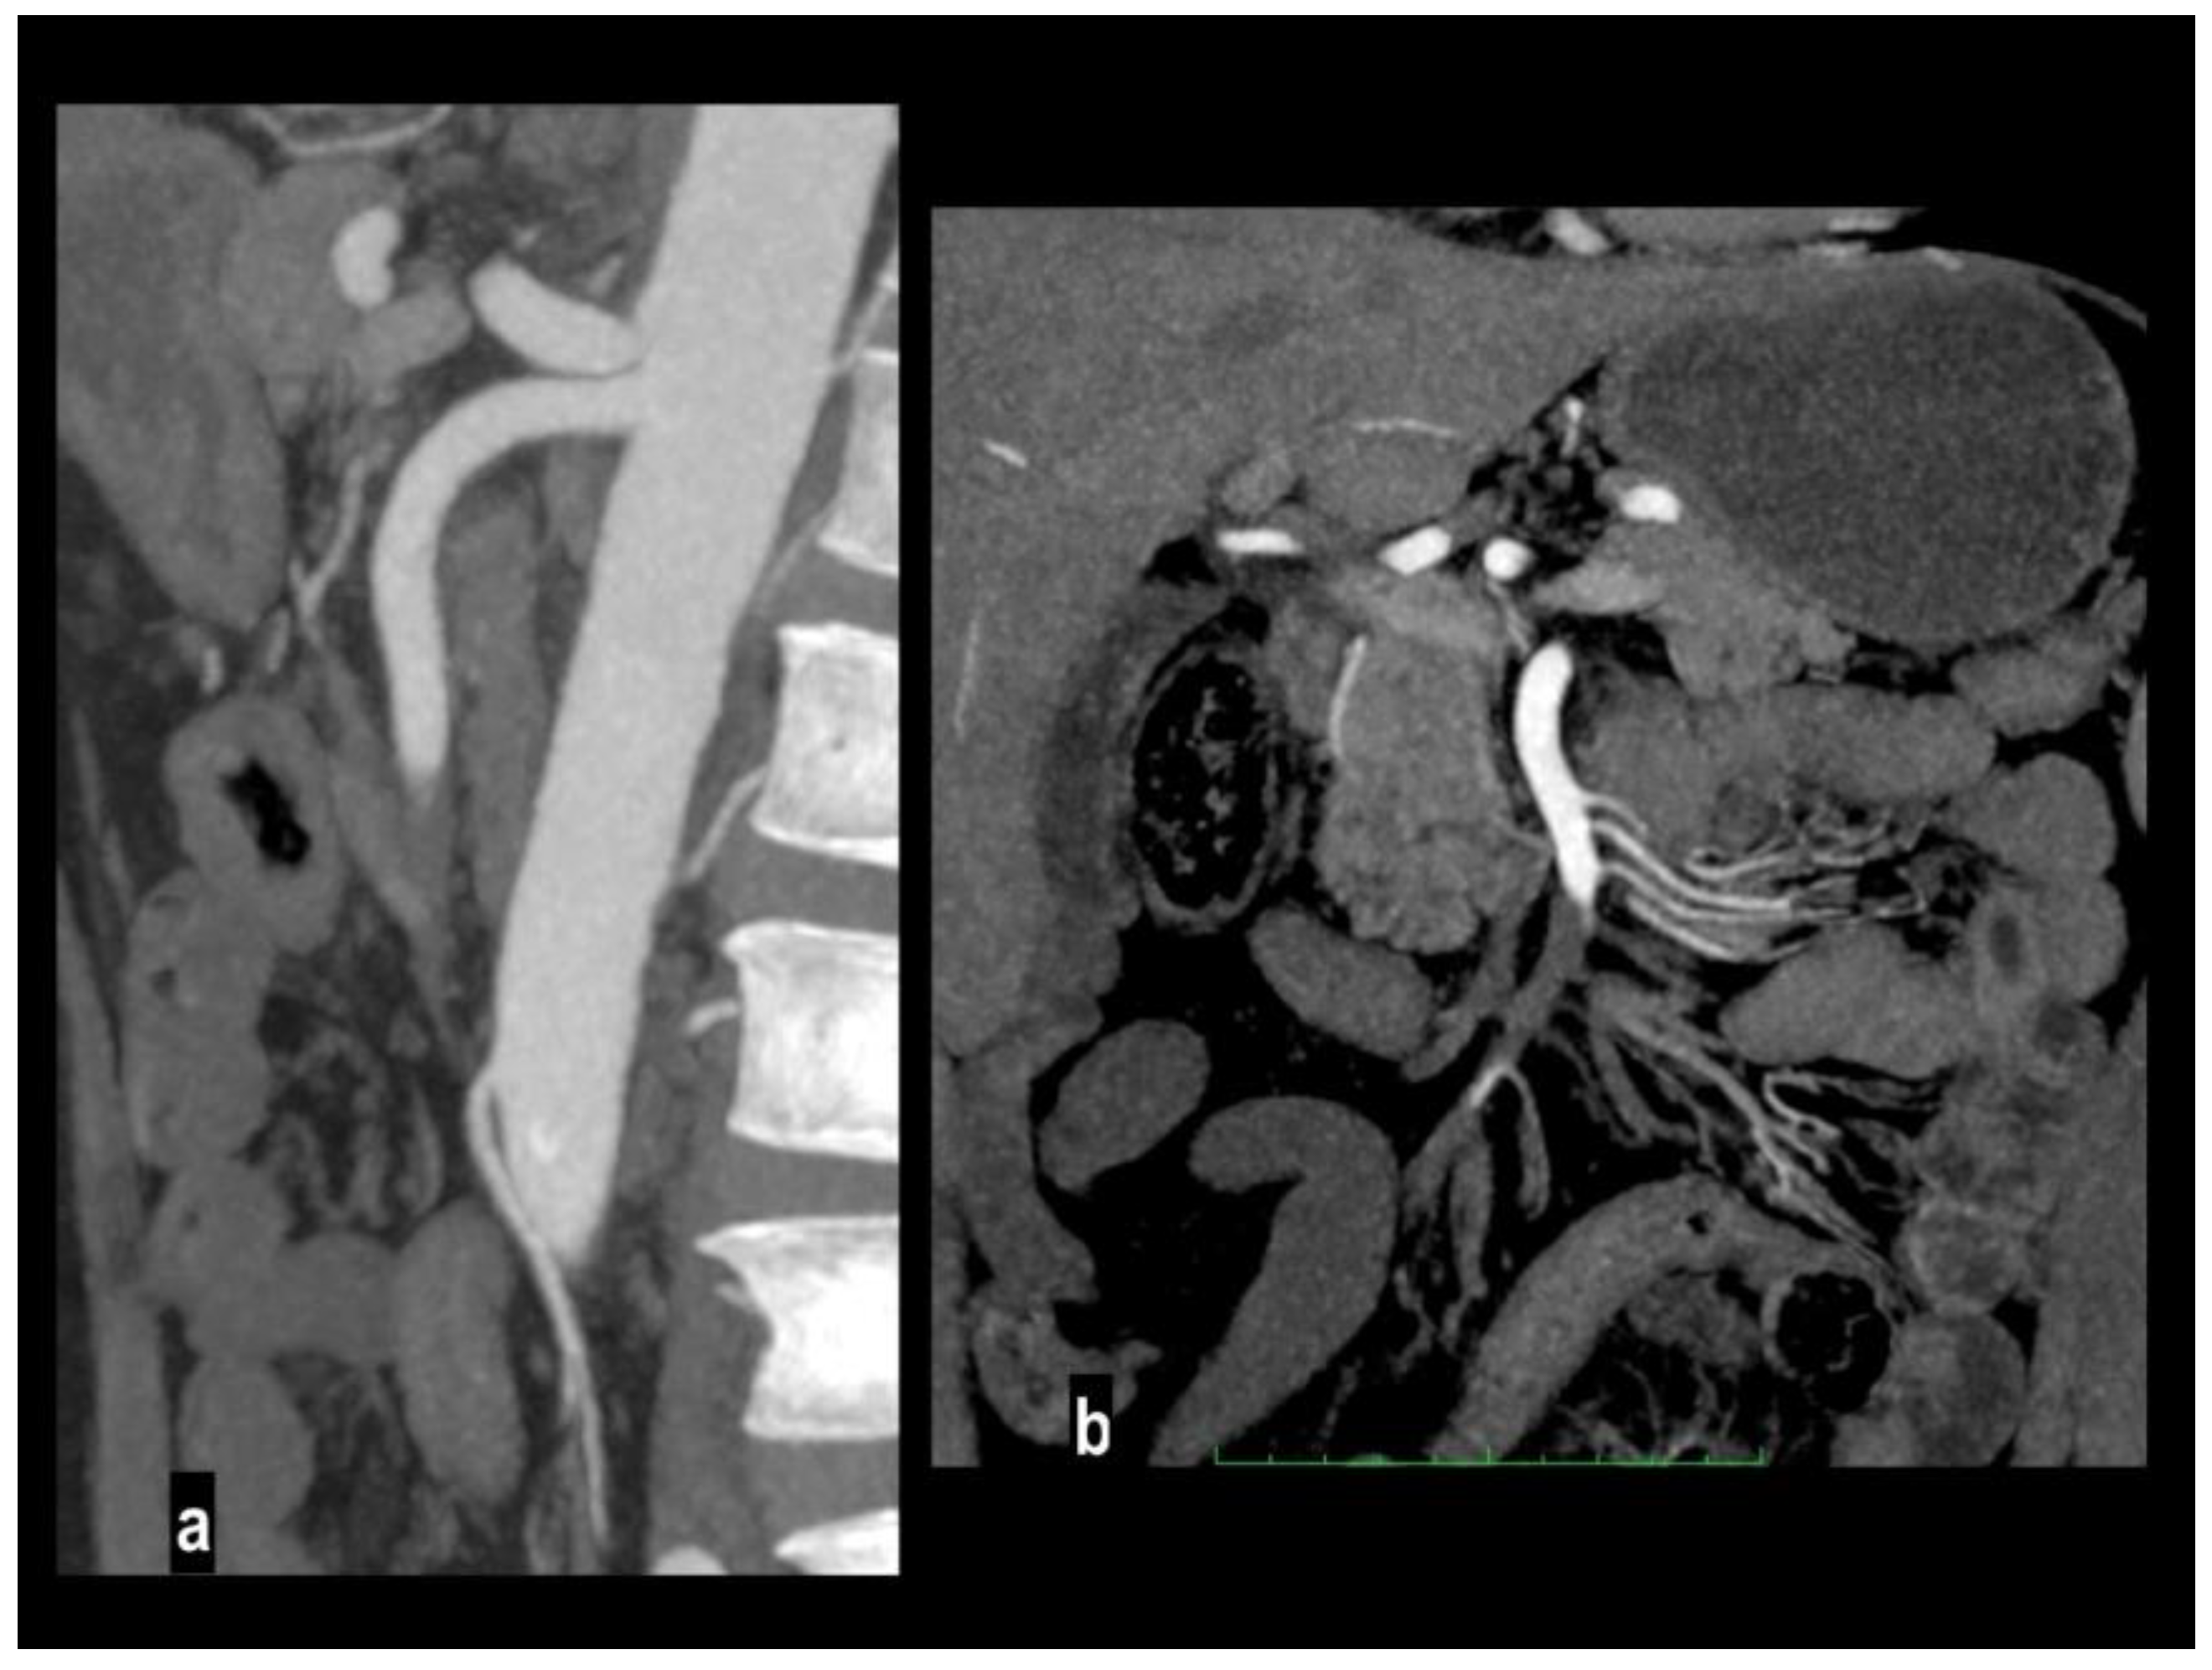

Figure 8. Acute abdominal pain in a 66-year-old woman. Atheromasic low-density plaque at the proximal SMA with luminal stenosis (figure 8a). Dilated paper-thin small bowel wall (figure 8b). Segmentary transmural necrosis is observed on the mesenteric side of an intestinal loop (arrow), intestinal wall line loss and periparietal fluid effusion (figure 8c). The patient underwent surgical resection of the necrotic loop.